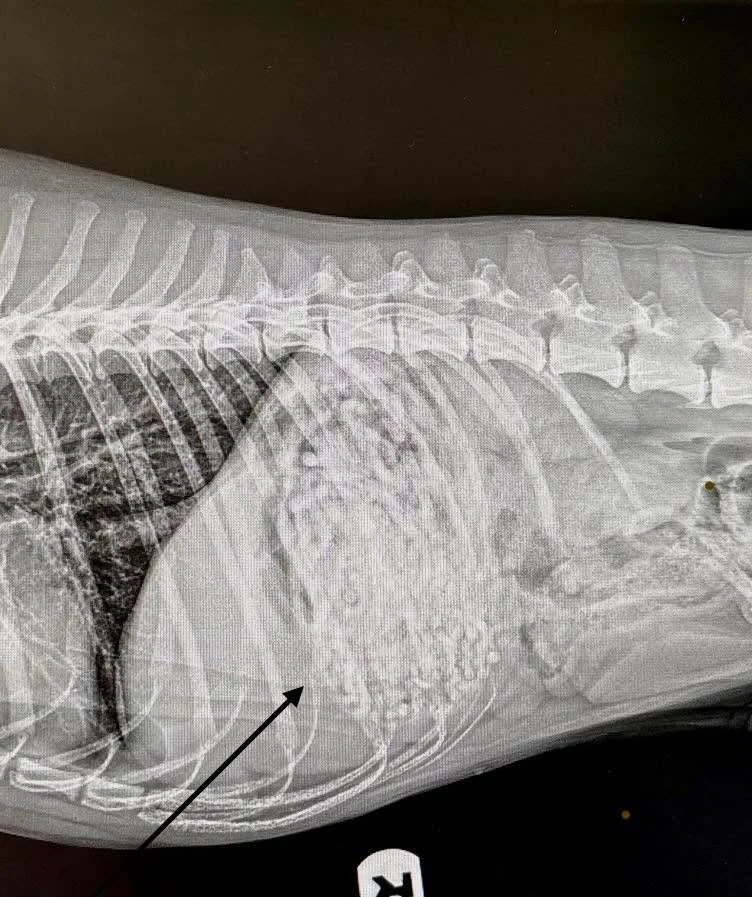

• Our sweet 16 year old man had some serious stomach issues this weekend and this place got in him last minute—cannot brag enough on the super sweet staff that got us in or the veterinary doctor himself for listening to our concerns. Our baby is already doing SO much better!!! (Plus the bill was way cheaper than most places!!) 10/10 recommend!!